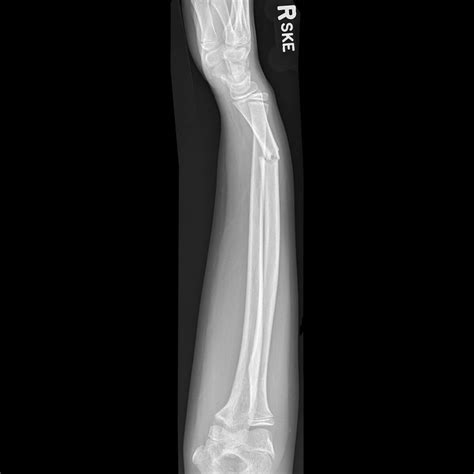

Diagnosing subluxation of radius involves a combination of physical examination and imaging tests. A healthcare provider will typically perform the following steps:

• Physical Examination: The doctor will assess the range of motion, strength, and stability of the forearm. They may also check for tenderness and swelling.

• Imaging Tests: X-rays, MRI, or CT scans may be ordered to visualize the bones and soft tissues. These tests can help confirm the diagnosis and determine the extent of the subluxation.